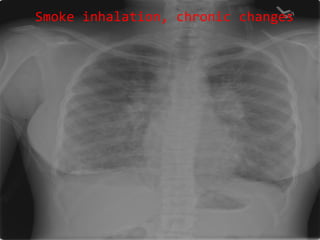

Smoke inhalation, chronic changes